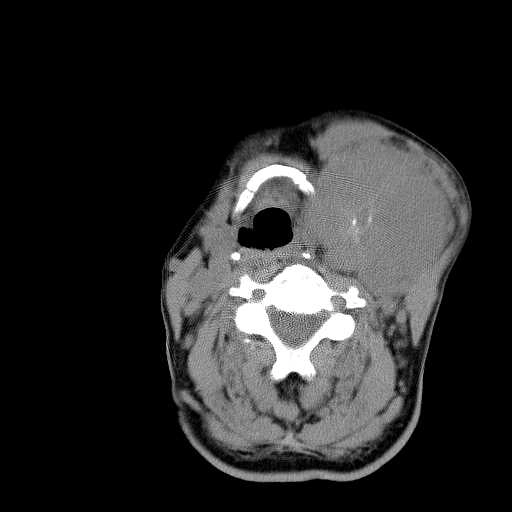

Sarcoma hoạt dịch vùng cổ (Synovial Sarcoma of Head and Neck)